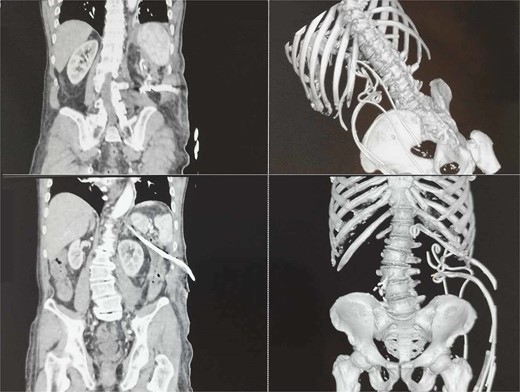

A subsequent microbiological examination showed no bacterial growth. Normal laboratory findings. Additional abdominal ultrasound and CT showed no significant remaining fluid collections (Fig. 2).

The patient recovered gradually, and no laparotomy was required. A follow-up CT after one month showed no residual collections (Fig. 3).